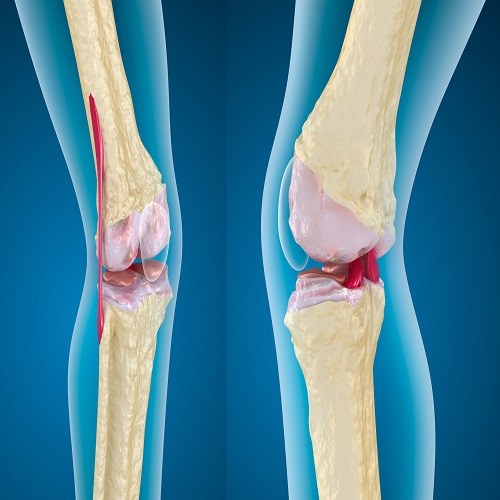

Artroskopik Menisküs Onarımı Nedir? Artroskopik menisküs onarımı, diz eklemindeki menisküs adı verilen kıkırdak dokusunun, minimal invaziv bir cerrahi prosedür olan artroskopi yöntemiyle onarılması işlemidir. Menisküs, diz eklemleri içinde bulunan C şekilli kıkırdak yapıdır ve ek yüzeylerin düzenli bir şekilde yük görünümünü sağlar. Ancak travma, aşırı zorlanma veya yaşlanmaya bağlı olarak menisküs yırtılabilir. Artroskopik menisküs onarımı,…